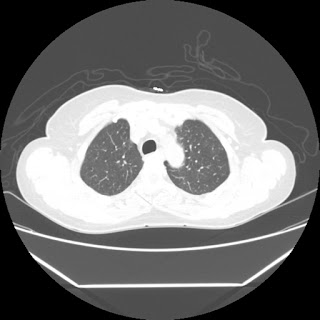

Radiological images:

HRCT is also done on 13/11/15